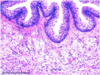

Identify: